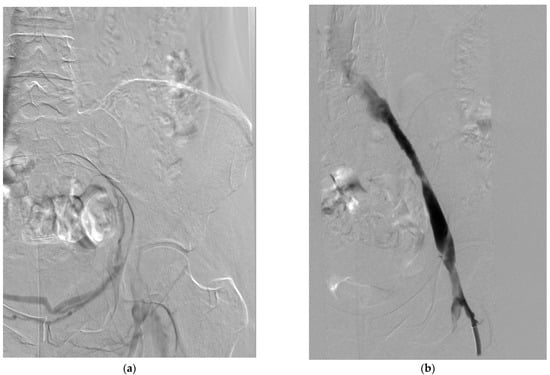

4.4. Venous Stenting

4.4.1. Indications and Technical Considerations

- Residual venous stenosis after thrombolysis/thrombectomy: Significant stenoses (>50% diameter reduction or pressure gradient >2 mmHg) may be treated with stenting to maintain patency and prevent rethrombosis [74].

- Extrinsic venous compression: May–Thurner syndrome (compression of the left common iliac vein by the right common iliac artery) is present in up to 50% of patients with left-sided iliofemoral DVT and typically requires stenting for long-term patency [84].

- Chronic post-thrombotic venous occlusion: In patients with established PTS and venous claudication, recanalization and stenting of chronic occlusions may improve symptoms and quality of life [85].